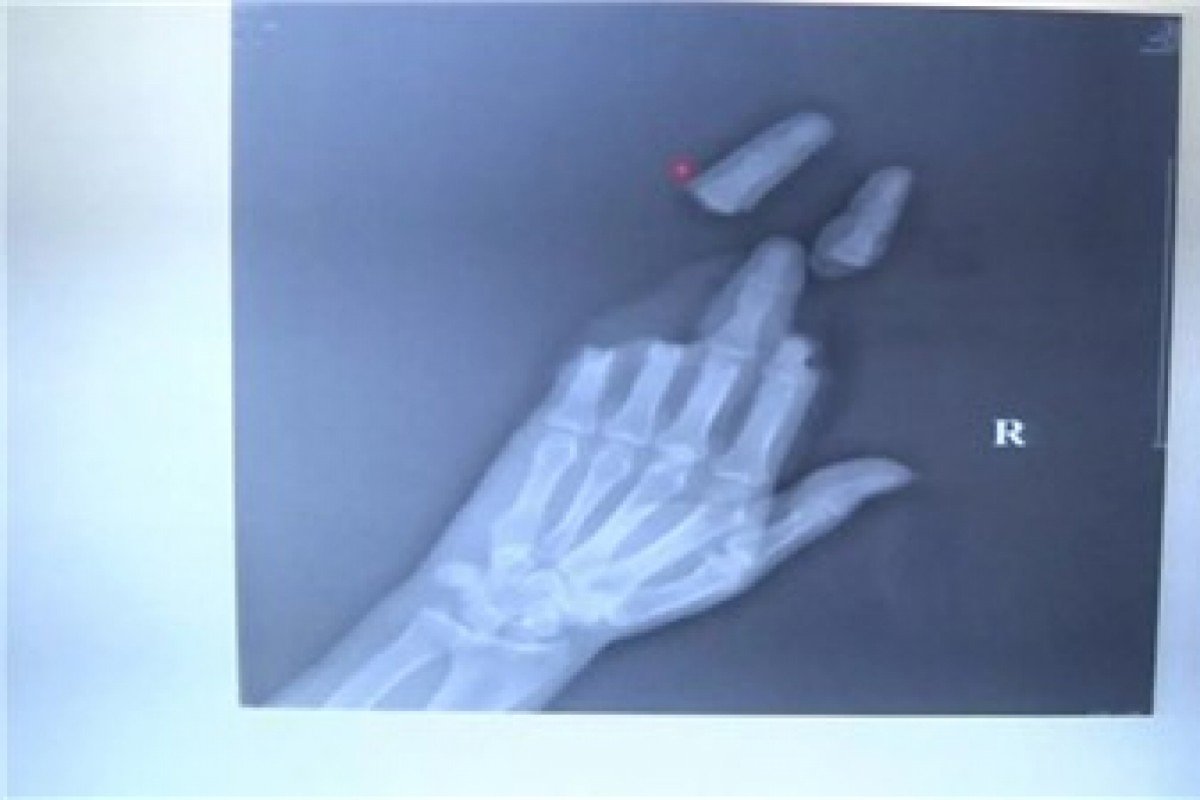

Ảnh chụp X-quang 3 ngón tay bị dây diều cắt đứt.

Jin Dejun, giám đốc Khoa phẫu thuật chân tay của bệnh viện chỉnh hình Nam Thông cho biết, khi nam thanh niên đến đây, ngón tay thứ 2 đến ngón tay thứ 5 đều bị cắt đứt. Tuy ngón giữa không bị đứt lìa ra nhưng đó chỉ là các phần xương kết nối với nhau, trong khi dây thần kinh và gân cơ đều đã bị cắt đứt.